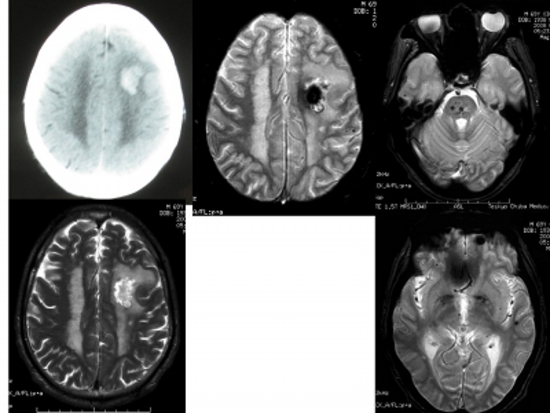

Figure 3

Head CT, MRI T2*-weighted image, T2-weighted image of left frontal subcortical hemorrhage.

T2*-weighted images (three images on the right) show numerous hidden cerebral hemorrhages in the brain stem, left frontal lobe, and left temporal lobe.